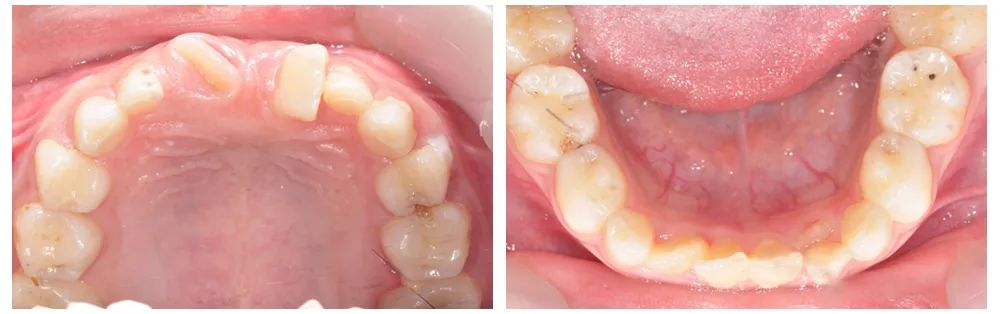

▲术前情况

▲术中情况